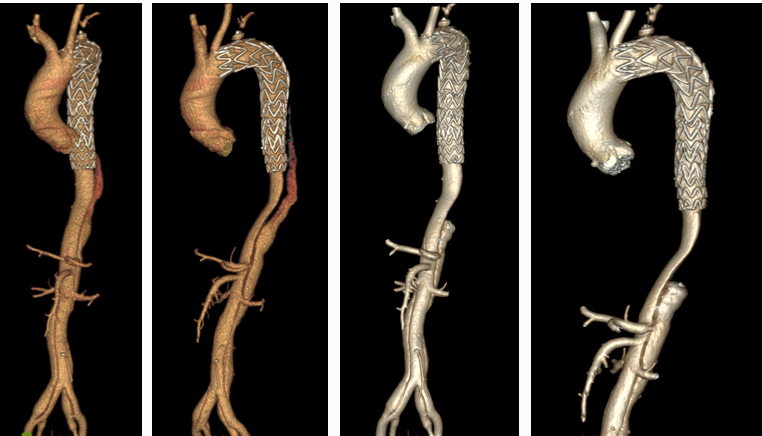

主动脉重塑差异与301分型

★ 术后转归差异

重塑差:假腔持续扩张,真腔受压(图文对照显示术后1年假腔未闭合)

重塑好:真腔恢复血流,假腔血栓化(影像显示术后1年假腔消失)